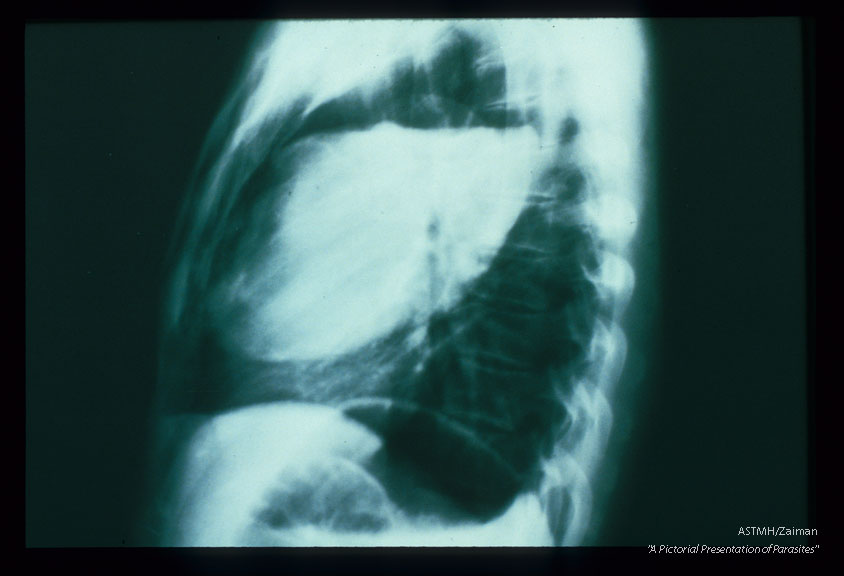

Frontal and lateral chest x-rays. A huge partially empty white cyst is present in the right lung of this patient. It's upper limits are marked by a white pencil-like line of calcium, Above the white fluid and below the white penciled line, the cyst is filled with air (black). This indicates communication between the cyst and a bronchus. Usually an air-fluid interface would be a neat line. In echinococcosis, the line is irregular due to floating collapsed membranes (from the dome of the cyst) and floating daughter cysts. This is the classic floating lily sign of pulmonary echinococcosis.

Echinococcus granulosus